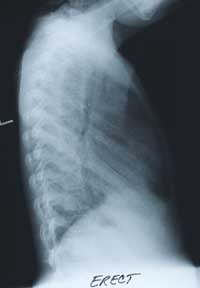

BELOW

is her CHEST X-RAY taken during the hospitalization.

Previous films from her NICU stay are not available.

Enlarge the CHEST X-RAY LEFT, enlarge the chest x-ray RIGHT.

WHAT ARE YOUR FINDINGS?